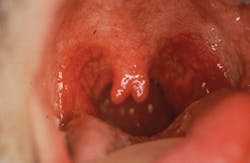

In recent years, the role of the uvula in snoring and in obstructive sleep apnea (OSA) has been a major issue with many studies underway. The uvula consists of connective and granular tissue with diffuse interdigitated muscle fibers.2 People with OSA have thicker, larger uvulas with more muscle and fat.2 A review by Chang et al. states that histologic analysis has shown people with OSA to have bulkier, more edematous uvulas with thicker epithelia and increased leukocytes when compared to samples from controls with no history of snoring.3 The authors question whether the increase in size or epithelium is due to the more rigorous motion experienced during snoring (figure 2).